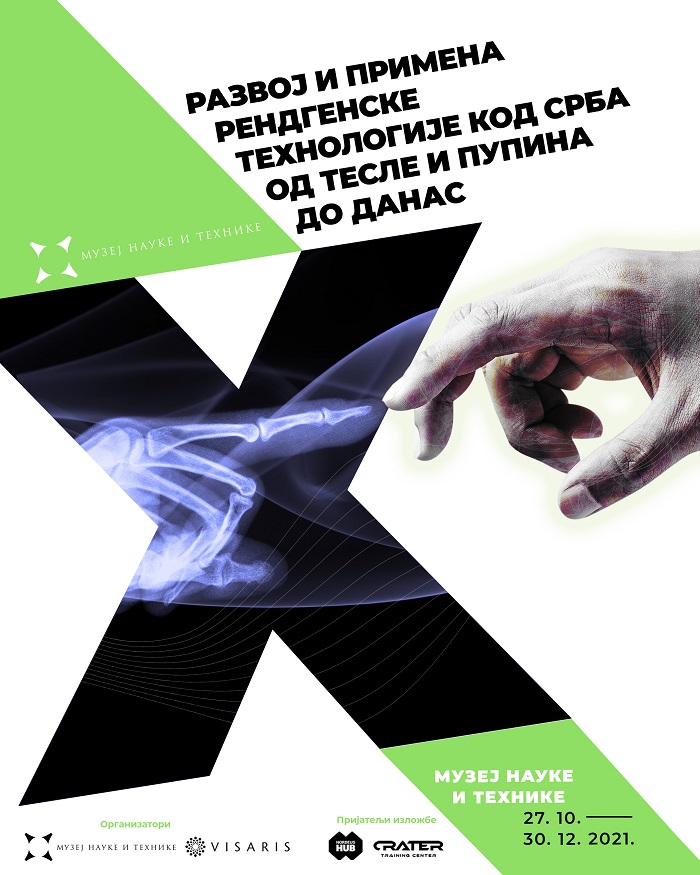

Muzej nauke i tehnike najavljuje izložbu Razvoj i primena rendgenske tehnologije kod Srba – od Tesle i Pupina do danas, koja će biti otvorena 27. oktobra u Galeriji 51, u Skender-begovoj 51. Izložbu organizuju Muzej nauke i tehnike i kompanija Visaris uz podršku Ministarstva za kulturu i informisanje Republike Srbije. Autori izložbe su Jelena Jovanović Simić i Aleksandar Vl. Marković; autori dizajna postavke su Ozarija Marković Lašić i Nebojša Vasiljević; grafički dizajn kataloga izložbe uradio je Miloš Janković, a muziku za izložbu komponovao je Aleksandar Vl. Marković. Edukativne digitalne igre za decu i omladinu kreirali su najbolji polaznici besplatnih obrazovnih programa za razvoj igara, prijatelja izložbe Nordeus Haba i Krater trening centra.

Izložba će predstaviti istorijski razvoj i primenu rendgenske tehnologije u medicini, od otkrića rendgenskih zraka do danas, sa posebnim naglaskom na doprinosima koji su u oblasti rendgenologije ostvarili Nikola Tesla i Mihajlo Pupin. Ciljevi izložbe su i predstavljanje uspeha domaćih preduzeća u razvoju proizvodnje rendgenskih aparata i opreme.

U drugoj polovini 20. veka, u vreme intenzivnog razvoja industrije u nekadašnjoj Jugoslaviji, fabrika Jugorendgen (u sastavu Elektronske industrije Niš), jedina je na Balkanu proizvodila rendgenske aparate i izvozila ih širom sveta. Nakon raspada Jugoslavije, kriznih devedesetih godina i kasnijih procesa tranzicije tokom kojih su prestala s radom mnoga industrijska preduzeća, među kojima je i Jugorendgen, grupa mladih stručnjaka je početkom novog milenijuma osnovala preduzeće Visaris i započela razvoj i proizvodnju nove generacije uređaja – digitalnih rendgenskih aparata. Kao i nekada Jugorendgen, Visaris je danas jedini proizvođač rendgenskih aparata u regionu, a takođe je prisutan i na svetskom tržištu.

Izložba prati put srpskih naučnika koji su dali izvanredan doprinos tokom druge industrijske revolucije krajem 19. veka sve do današnjeg perioda digitalne transformacije i novog talasa doprinosa naših stručnjaka u aktuelnoj četvrtoj industrijskoj revoluciji na globalnom nivou u kojoj srpska nauka na polju digitalne medicine i ostalih segmenata digitalne tehnologije ostvaruje značajne rezultate.

Osim što će promovisati srpska naučna dostignuća u ovoj važnoj oblasti medicinske dijagnostike i terapije, ciljevi izložbe su i unapređenje znanja iz oblasti istorije medicine i istorije razvoja industrije u Srbiji i popularizacija nauke, posebno među generacijama koje odrastaju u sadašnjem digitalnom dobu.

Pored fotografija i dokumenata, na izložbi će moći da se vide i stari rendgenski aparati, oprema i sredstva za ličnu zaštitu od zračenja, prve rendgenske cevi proizvedene u Jugoslaviji, ali i najnoviji digitalni rendgenski uređaji. Sastavni deo izložbe su sadržaji u obliku virtuelne stvarnosti (VR) i edukativne digitalne igre za decu i omladinu koje su kreirali najbolji polaznici besplatnih edukativnih programa za razvoj igara, prijatelja izložbe Nordeus Haba i Krater trening centra. Tokom trajanja izložbe biće organizovana stručna vođenja, predavanja i edukativne radionice za decu, omladinu i studente.